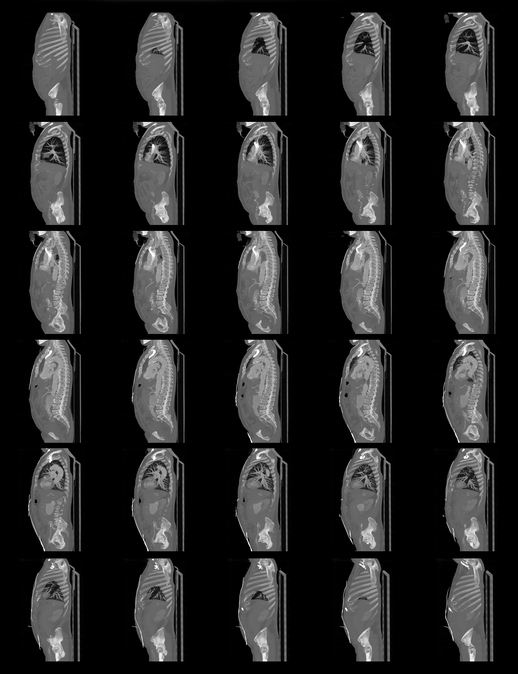

From www.researchgate.net

Image examples of a wholebody lowdose CT scan (a scout). Images were... Download Scientific How Long Is A Full Body Ct Scan A ct scan can see nearly all parts of the body. A ct scan can take anywhere from 10 to 30 minutes, depending on what part of the body is being scanned. The procedure takes less than 30 minutes and generally includes these steps: You will undress and put on a patient gown. The images need to be looked at. How Long Is A Full Body Ct Scan.